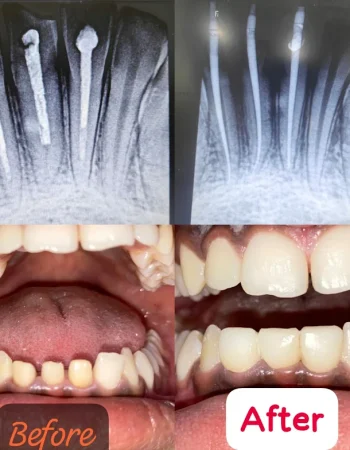

Dr. Anu’s Tooth Care Dental Clinic is committed to delivering comprehensive and affordable dental care for the entire family. We specialize in general dentistry, cosmetic dentistry, root canal treatment, orthodontics (braces & aligners), dental implants, pediatric dentistry, teeth whitening, gum care, and preventive treatments. With a focus on painless procedures, modern equipment, and strict hygiene standards, our clinic ensures every patient receives safe and effective care in a comfortable environment. Dr. Anu and the team provide personalized treatment plans to restore, protect, and enhance your smile. Whether it’s a routine check-up, corrective dental work, or a complete smile makeover, we are here to care for your oral health with expertise and compassion.